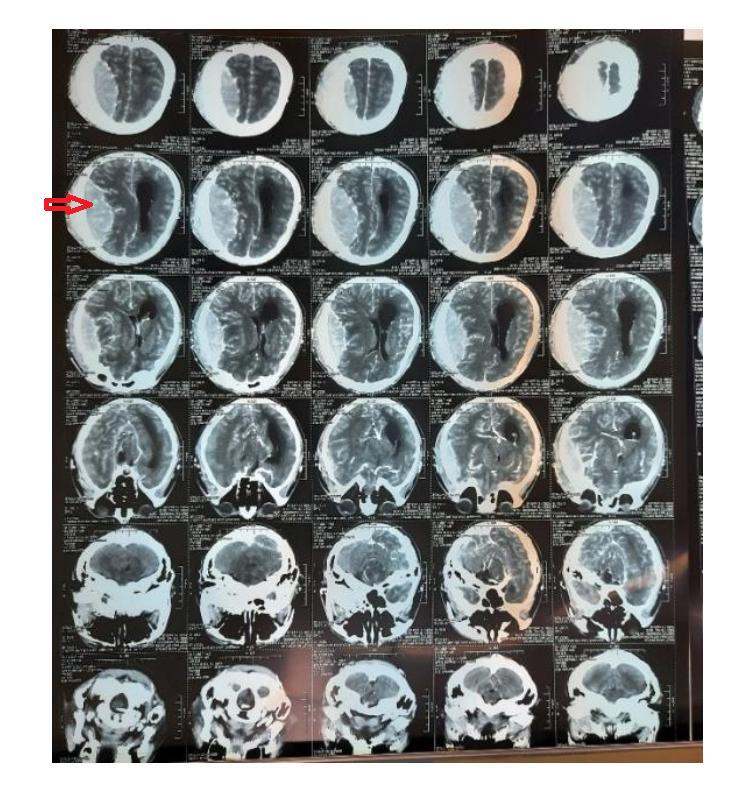

Hình ảnh sau phẫu thuật |

Đối với bệnh nhân này, bệnh xác định cần mổ cấp cứu, không thể chậm trễ. Ê kíp phẫu thuật với sự hỗ trợ của kính vi phẫu đã lấy trọn toàn bộ khối u đồng thời bảo tồn các mạch máu não. Hiện, bệnh nhân đã tỉnh, tiếp xúc tốt. Sự hồi phục kỳ diệu của bệnh nhân mang lại niềm vui không thể diển tả của tập thể thấy thuốc bệnh viện và người nhà bệnh nhân.